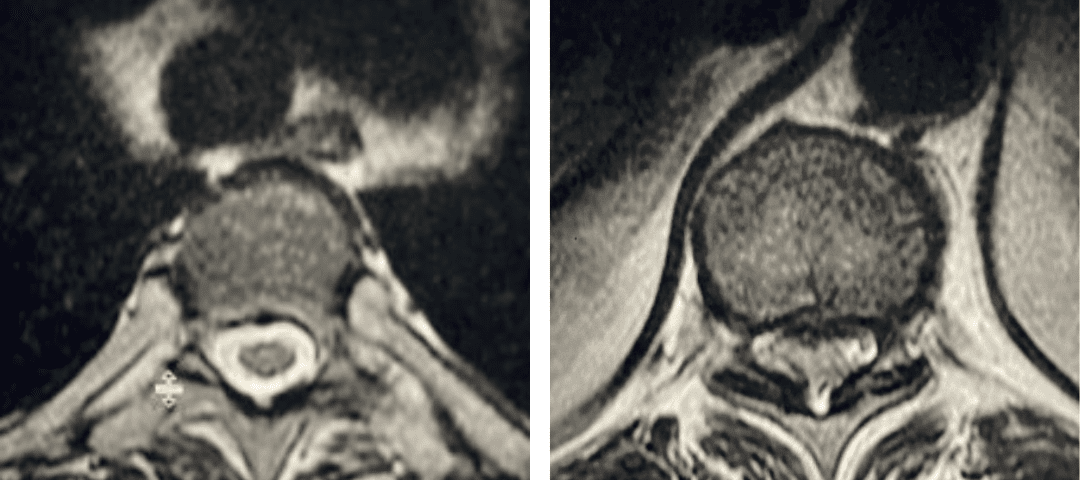

Figure 2. Axial images comparing a normal appearing spinal cord with a white fluid ring around it versus an axial image of the T10-11 level demonstrating circumferential stenosis.

This 50-year-old morbidly obese female presents with one month of progressive weakness of her lower extremities. She also reported numbness and pain in her thighs. Her right leg was worse, and she had one episode of urinary incontinence. She had some back pain. She was ⅖ strength in her right hip flexor and quadriceps. She was ⅘ in her left lower extremity. MRI (Figure 1 and Figure 2) revealed very tight stenosis circumferentially at T10-11 secondary to facet hypertrophy and anterior disc osteophyte complex with associated myelomalacia of the spinal cord. There was also stenosis to a lesser degree but still significant at the T11-12 level.